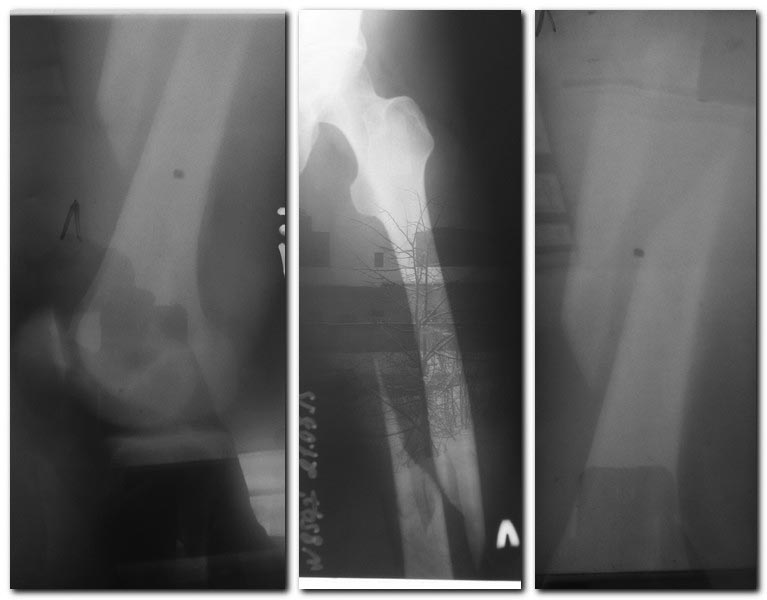

У больной оказалась узкая часть к.м.канала=9мм. по Rn-граммам здорового бедра. Поэтому сделали открытую репозицию, накостный синтез. П/о Rn-граммы прилагаю.

После операции.